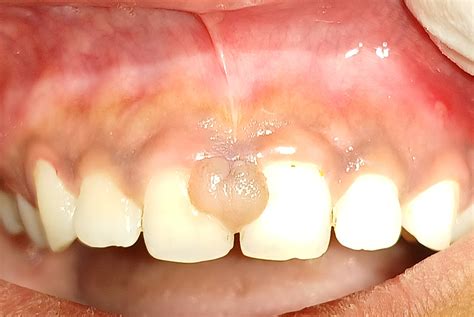

En la mayoría de los casos, se origina como consecuencia de una respuesta hiperplásica del tejido conjuntivo frente a irritaciones físicas, químicas o mecánicas de carácter repetitivo. Llamamos fibroma a un bulto, generalmente redondo, que se encuentra sobre la superficie gingival y que aparece en alguna zona blanda que está bajo irritación constante.

Mediante las visitas al odontólogo en Salamanca se detecta su presencia para tratarlo antes de que se vuelva más incómodo. Un fibroma encía es un crecimiento benigno de tejido fibroso.

El fibroma bucal se manifiesta clínicamente como una lesión nodular de tamaño variable que puede oscilar entre los 5 mm y los 2 cm de diámetro. El fibroma oral se presenta como una pápula suave y firme en la boca. Suele ser del mismo color que el resto del revestimiento de la boca, pero a veces es más pálido o, si ha sangrado, puede tener un color oscuro. Su superficie externa puede ulcerarse debido a un traumatismo o volverse áspera y escamosa. Por lo general, tiene forma de cúpula, pero puede tener un tallo corto como un pólipo (pediculado).

El fibroma osificante periférico suele verse como un crecimiento del tejido blando localizado en la papila interdental. El fibroma se manifiesta como una elevación de consistencia dura en los tejidos blandos orales, normalmente no cursan con dolor y suelen ser simplemente incómodos.